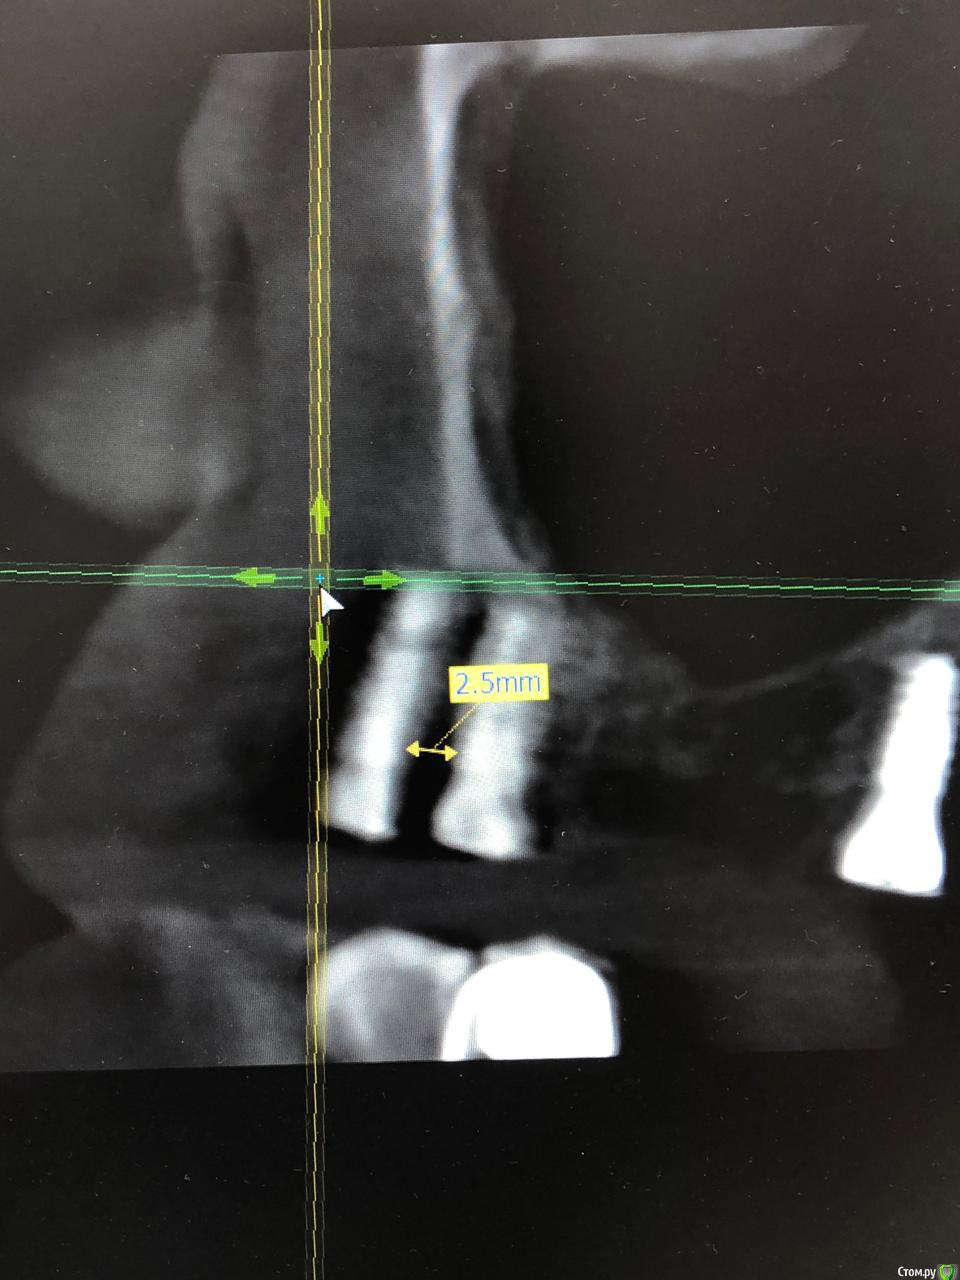

ALLA0105 Опубликовано 2 февраля, 2020 Автор Поделиться Опубликовано 2 февраля, 2020 Здравствуйте! Была у доктора, отправил на КТ ,чтобы определить точное расстояние. Он может по моему настоянию переставить имплант, но не считает это целесообразным. Говорит, что дает гарантию. Вот, что он мне прислал. Расстояние 2,5мм и 2,8 мм. Подскажите, а гарантию надо в договоре прописать? И на какое количество лет надо прописать гарантию , если соглашусь оставить все как есть? Ссылка на комментарий